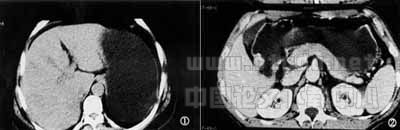

1.3 方法 患者于检查前6h禁食,扫描前20min肌注654-2 20mg,而后喝温开水1000~1200ml。先取仰卧位平扫自膈顶扫至第3腰椎水平,部分胃张力较低患者扩大扫描范围。然后,根据患者病变部位选取左侧卧位(胃底贲门部病变)或右侧卧位(胃体及胃窦部病变)重复扫描,见图1。再利用高压注射器注入60%泛影葡胺100ml做增强扫描,注射速率为2.8~3.0ml/s。根据胃癌CT表现,我们将胃癌按表1标准分期,见图2~4。

图1 胃低张服水1200ml后扫描示胃底部正常胃壁厚度。

图2 胃窦部胃癌Ⅰ期,胃窦部腔内局灶性结节,胃壁无明显增厚。

图3 胃窦部胃癌Ⅱ期,胃窦部胃壁增厚>1.0cm,胃壁线僵硬,并腔内结节。